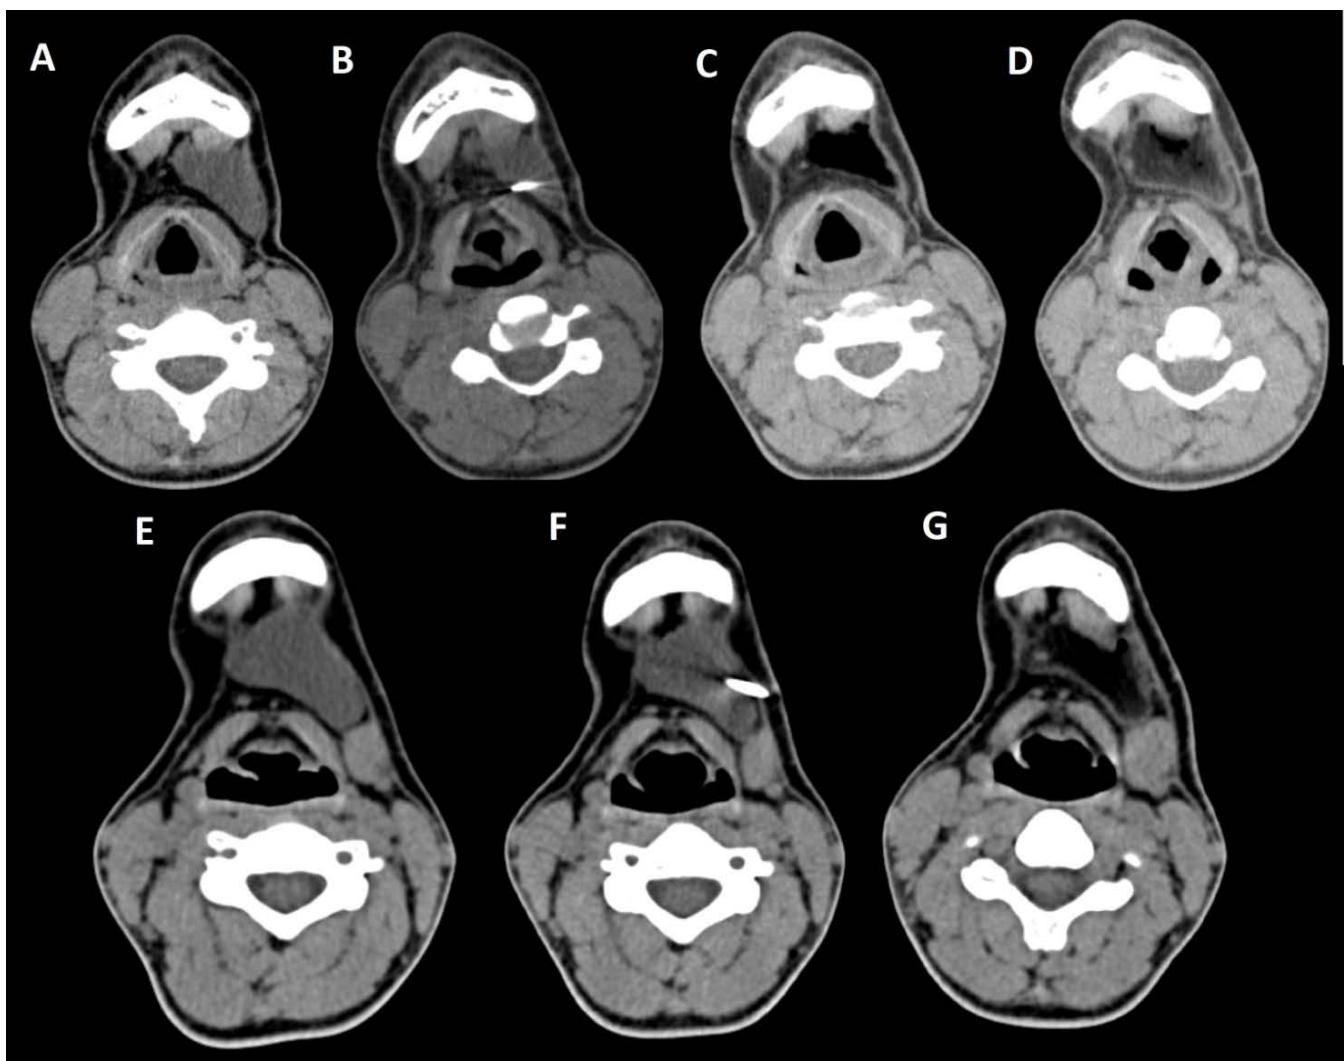

Figure/Patient 4

1. A 7 year-old girl presenting with a tumefaction at the level of the left latero-cervical region. MRI scans show a subcutaneous lesion occupying the left submandibular, parotidal, para-pharyngeal and part of the masticatory spaces. The lesion appears slightly hyper-intense on T1 (A-C) and markedly hyper-intense on T2 (D-F) scans. Diagnosis of cystic lymphangioma is done.

2. The same patient undergoing two different sessions (A-D and E-G, respectively) of sclerotherapy with absolute ethanol. An 18-G needle is introduced into the lesion and about 10 cc of citrine-turbid fluid are aspirated (B and F). Then, 5 cc of ethanol are injected and the patient is mobilised in order to distribute the SA throughout the lesion (D and G). The patient is dismissed and a one-week antibiotic therapy is prescribed.